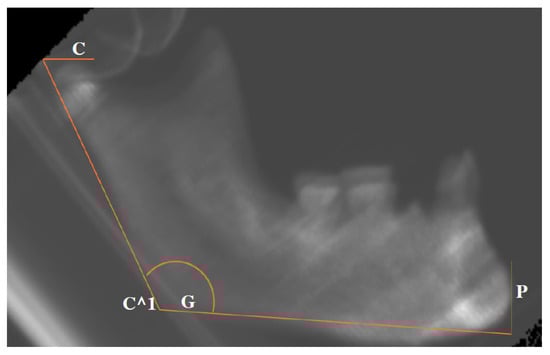

The .dcm files obtained by the CT scanning were processed with the open-source software Blue Sky Plan 4 (Blue Sky Bio Inc., Libertyville, IL, USA), which facilitated the implementation of a measurement protocol. Specifically, it was possible to build a latero-lateral radiograph for each of the mandibles. For each one, the following anatomical landmarks were identified: (a) Pogonion (the most anterior and prominent point of the horizontal ramus, Point P); (b) Gonion (Mandibular angle, the point of transition between the lower edge of the horizontal ramus and the vertical ramus), Point G; (c) Superior margin of the condyle (identified by the plane passing through the upper border of the condyle and parallel to the lower edge of the mandible), Point C. From the intersection between the plane passing through Point C and that passing through Point G and the posterior edge of the vertical ramus, Point C^1 is derived.

Once the landmarks were identified, the following segments were measured in millimeters: PG, from Pogonion to Gonion; PC^1, from Pogonion to Point C^1.

To measure the divergence between the vertical and horizontal branches of the mandible, the angle C^1-G-P was measured in degrees (Figure 2).

Figure 2. Graphical representation of the measurements taken from the latero–lateral projections. The location of each C, C^1, G, and P is referred to in the main text.

Figure 4. Latero-lateral projection of PbT12,1 mandible from the Archeo group, with the lines evoking the measurements for AR, HR and MA.